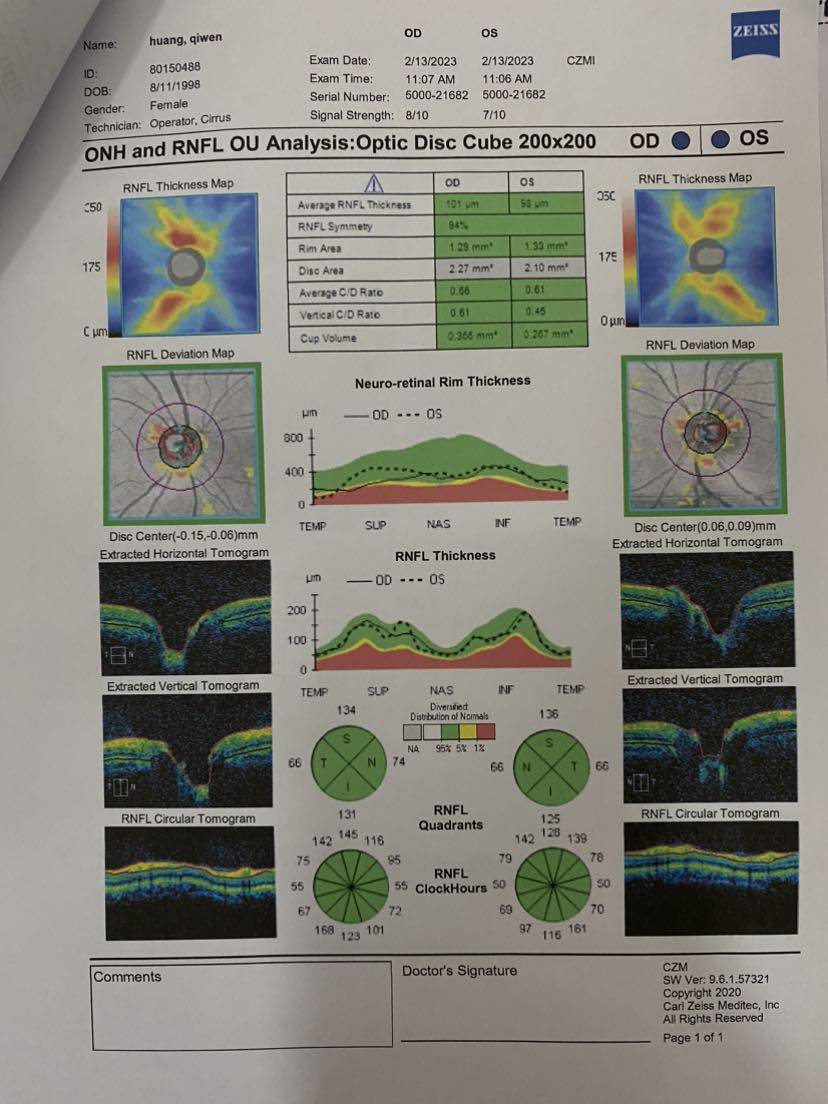

最后把所有报告记录一下,医生说要保管好。千万不能折,那就拍照先留个底吧~

【眼部ct】

哇,这个报告好仔细。

第一次看到这么详细的报告!蛙蛙下次去风湿免疫科复查的时候问问看~